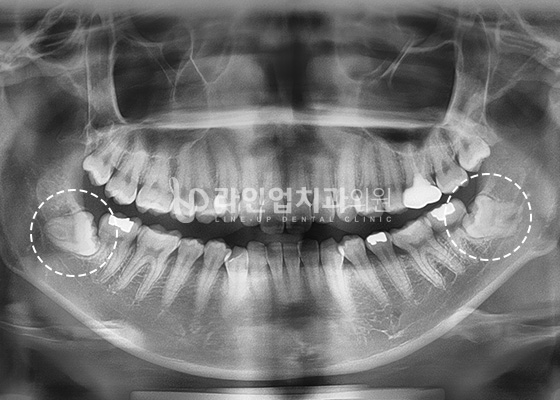

치료전 Before

치료후 After